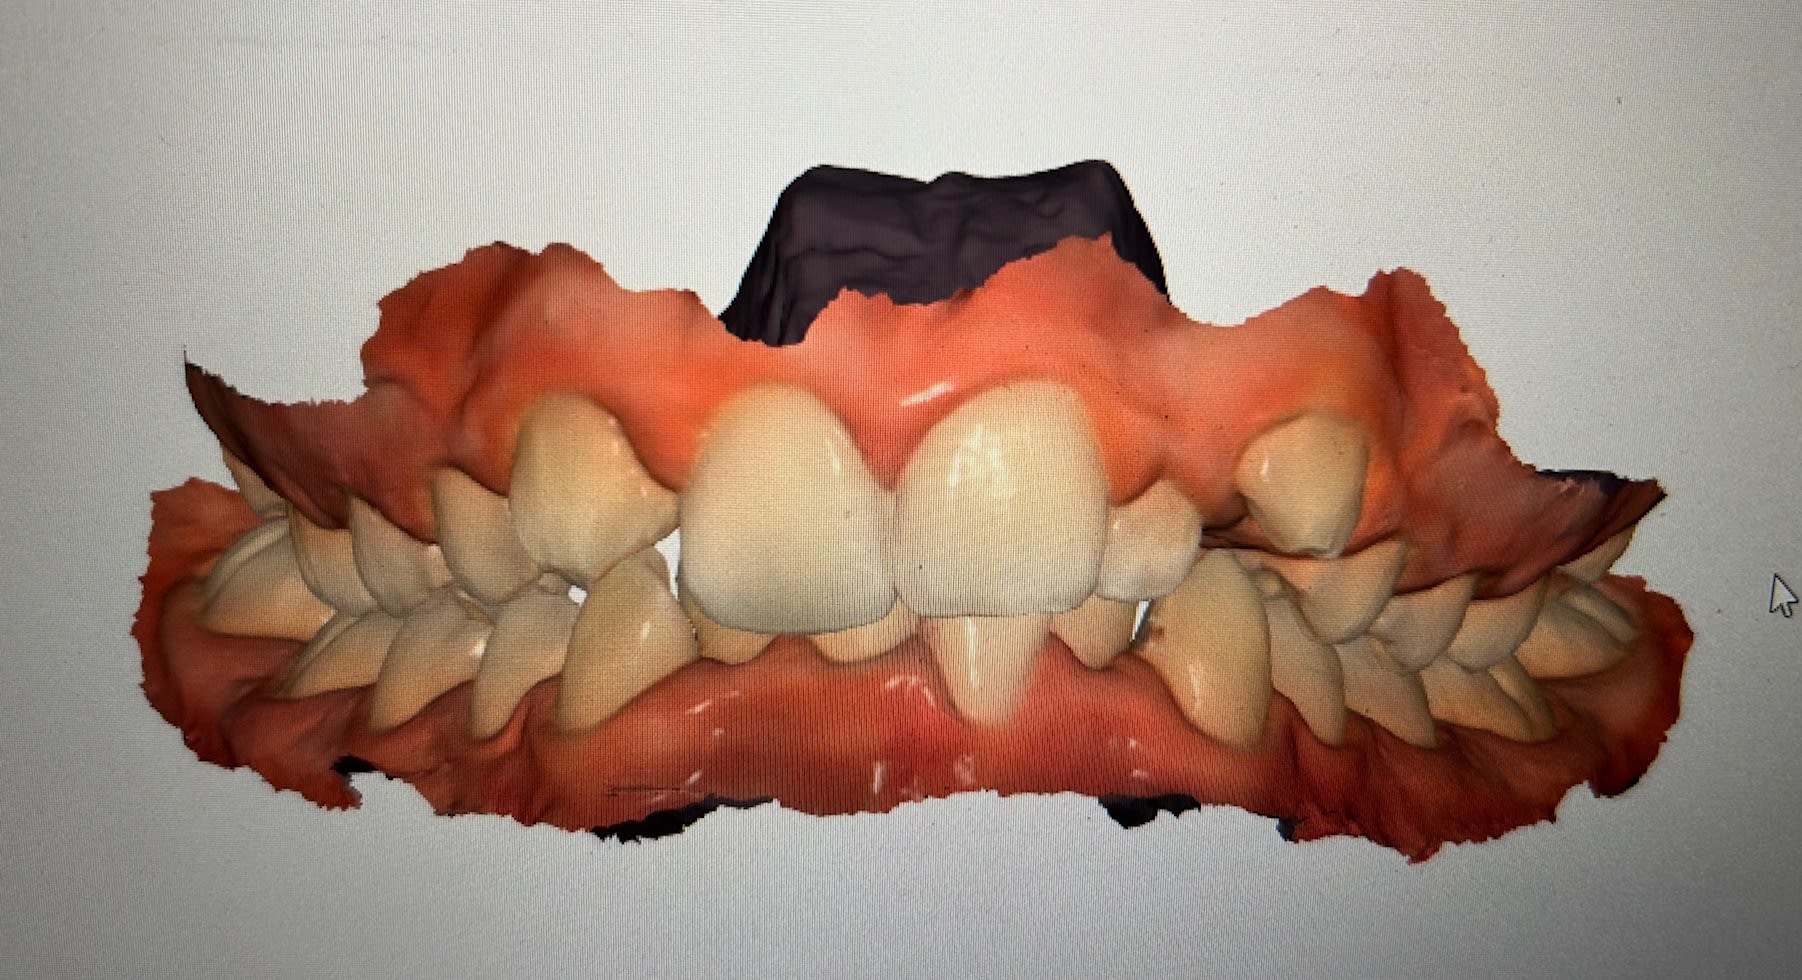

Jeune fille de 11 ans et demi, hypodivergente tendance classe III squelettique (mais classe II dentaire) et biretroalveolie. Agénésie de 12 avec évolution de 13 à sa place et 22 rhyziforme.

Vous partiriez plutôt à faire un alignement sans extraire 22 et conserver 13 en place de 12?

Procéder à l’alignement et conserver 22 et 13 en place de 12 peut être la meilleure solution selon vous ?

Recul secteur 1 & 2 : correction Cl II et ouverture espace 12 pour futur implant. C’est trop moche une canine d’un coté et une latérale de l’autre coté. Presque aussi moche que des canines à la place des latérales 🧛‍♂️

On finit en classe II canines thérapeutiques avec des coronoplasties de 13 et de 23.

Si les coronoplasties sont bien faites, ça passe très bien.